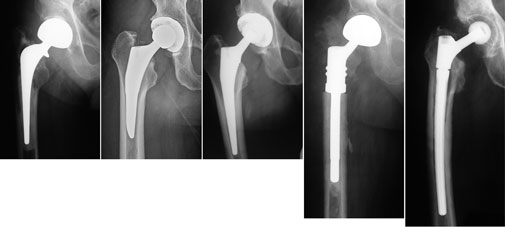

Hüftendoprothesen im Röntgenbild

Im Röntgenbild: Beispiele einer Versorgung mit Hüftendoprothese